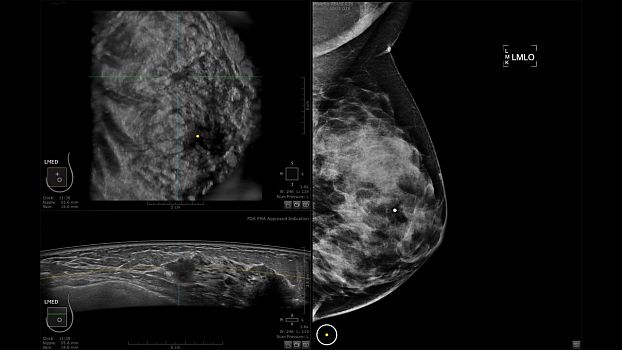

Клинические изображения

• Отображение объемных 3D ультразвуковых изображений, которые состоят из традиционных поперечных и воссозданных коронарных и сагиттальных проекций

• Возможность отображения полного 3D изображения

• Одновременный просмотр двух изображений для сопоставления в коронарной плоскости